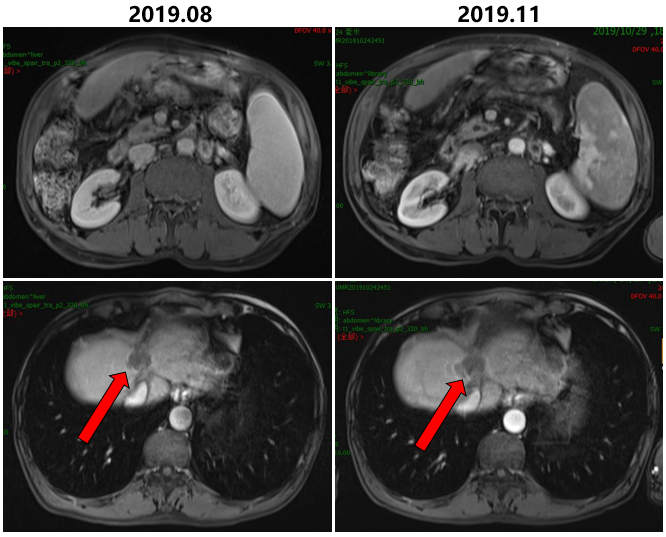

2019.08-2019.11继续行瑞戈非尼联合PD1单抗Keytruda。

治疗前后病灶变化情况

2019.11.04始予以行肝脏病灶射波刀放疗48GY/8F。

继续行瑞戈非尼联合PD1单抗Keytruda。